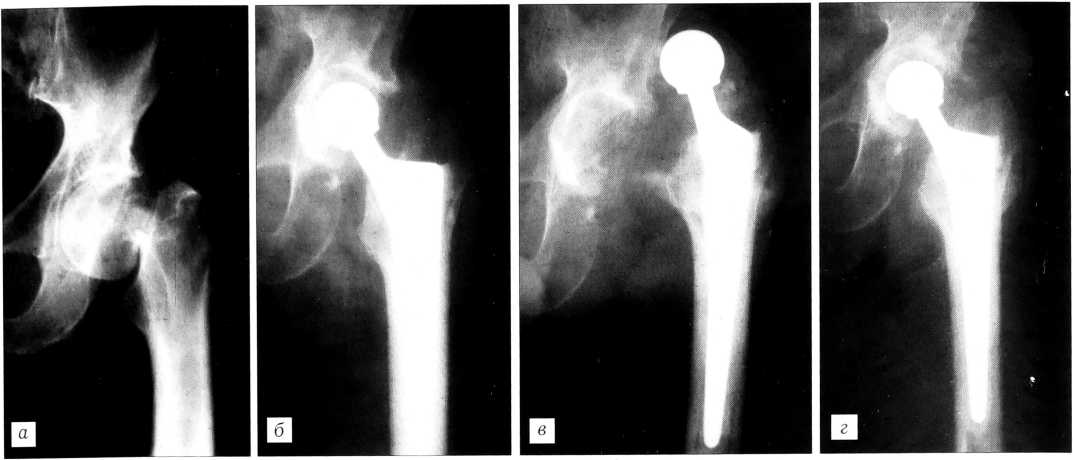

При поступлении больной жалуется на сильные боли в левом тазобедренном суставе, нарастающие при движении. Ходит с помощью костылей. Имеется относительное укорочение левой нижней конечности на 4 см. Оценка по Харрису 15 баллов. На рентгенограмме левого тазобедренного сустава определяется ложный сустав шейки бедренной кости, остеопороз (рис. 2, а).

19.12.97 под проводниковой эпидуральной анестезией выполнено тотальное эндопротезирование левого тазобедренного сустава с фиксацией компонентов на костном цементе (рис. 2, б). В послеоперационном периоде применялась клиновидная подушка между ног в течение 7 дней. Рана зажила первичным натяжением. Вставать с постели и ходить с помощью костылей больной начал со 2-го дня после операции. В удовлетворительном состоянии выписан на амбулаторное лечение по месту жительства.

Со слов больного, 20.01.98 (через месяц после операции) почувствовал резкую боль в суставе. За медицинской помощью не обращался, ходил при помощи костылей, не наступая на левую ногу. Задневерхний вывих бедра был диагностирован спустя 2 мес после его возникновения при контрольном осмотре в институте (рис. 2, в). Больной госпитализирован в клинику для оперативного лечения. 6.04.98 произведено открытое вправление вывиха с удалением значительных по размеру оссификатов, головка с короткой шейкой заменена на головку со средней шейкой. В течение 10 дней применялась клиновидная подушка между ног во время сна. Вставать на ноги и ходить разрешено на 5-й день после операции. Рана зажила первичным натяжением. Для профилактики гетеротопической оссификации назначен индометацин по 0,025 г 3 раза в день в течение 3 мес.

Контрольный осмотр спустя 5 мес после открытого вправления: ходит с помощью двух костылей, приступая на оперированную ногу, жалобы на боль во время длительной ходьбы, рентгенологически нарушений положения компонентов эндопротеза не выявлено, гетеротопическая оссификация отсутствует. Оценка по Харрису 62 балла. Рекомендованы лечебная гимнастика, массаж, ходьба с помощью трости. Контрольный осмотр спустя 1 год 4 мес: при ходьбе использует трость, боль не беспокоит, объем движений в суставе удовлетворительный, на рентгенограмме левого тазобедренного сустава признаков нестабильности компонентов эндопротеза и гетеротопической оссификации нет (рис. 2, г). Оценка по Харрису 79 баллов. Результат лечения больного, несмотря на застарелый вывих эндопротеза и его открытое устранение, считаем хорошим.

Рис. 2. Рентгенограммы больного Ф. а — до операции: ложный сустав шейки левой бедренной кости; б — состояние после тотального эндопротезирования левого тазобедренного сустава протезом конструкции УкрНИИТО с фиксацией на костном цементе; в — застарелый вывих головки эндопротеза. Обширные параартикулярные оссификаты; г — состояние после ревизии эндопротеза левого тазобедренного сустава (удалены гетеротопические параартикулярные оссификаты, головка протеза вправлена во впадину).